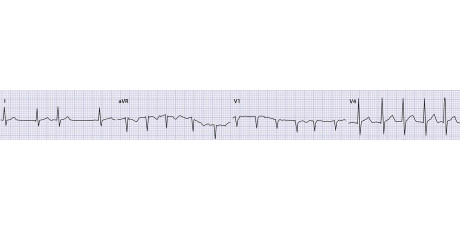

Een aanrader voor huisartsen die ervaring hebben met ECG’s en hart- en vaatziekten. Het leerboek bestaat uit vier onderdelen: indicatie en kwaliteit van ECG-beoordeling, basale elektrocardiografie, systematische beoordeling volgens ECG 10+ -methode en een appendix met begrippen en…